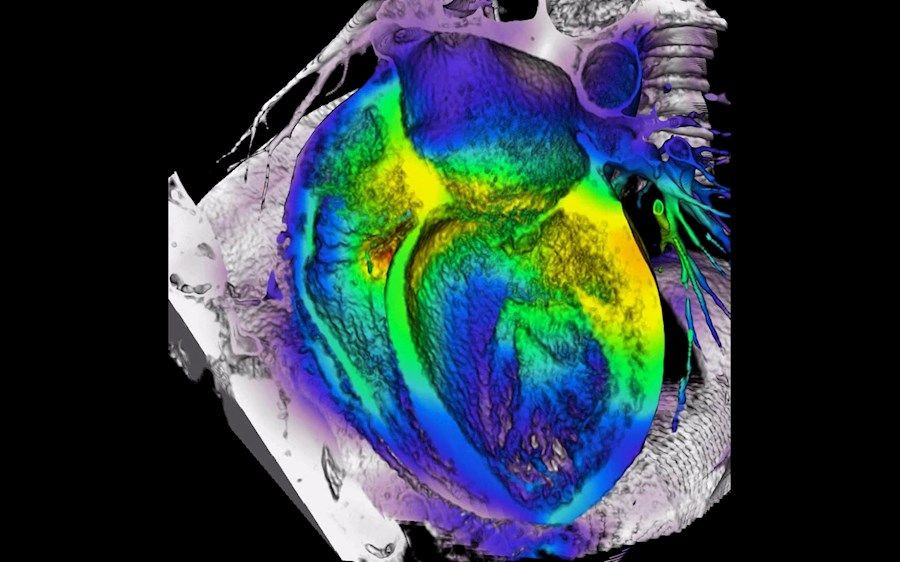

Una nueva investigación de la Universidad Estatal de Carolina del Norte muestra que las micropartículas de plaquetas son una forma efectiva de administrar medicamentos terapéuticos directamente al corazón después de un ataque cardíaco.

El daño de un ataque cardíaco no se detiene cuando finaliza el evento inicial. Después de un ataque cardíaco, las células inflamatorias liberan una proteína llamada Interleucina-1beta (IL-1beta), que induce una respuesta inflamatoria y promueve la cicatrización en el corazón con el tiempo. Los fármacos bloqueadores de IL-1beta han demostrado ser prometedores en los ensayos clínicos de fase tres, pero tienen riesgos y efectos secundarios significativos.

Además, los ratones que recibieron la terapia farmacológica dirigida recuperaron el 50% de la función cardíaca después de 70 días, en comparación con el 25% de recuperación en los ratones que recibieron la aplicación tradicional (no dirigida) del medicamento.